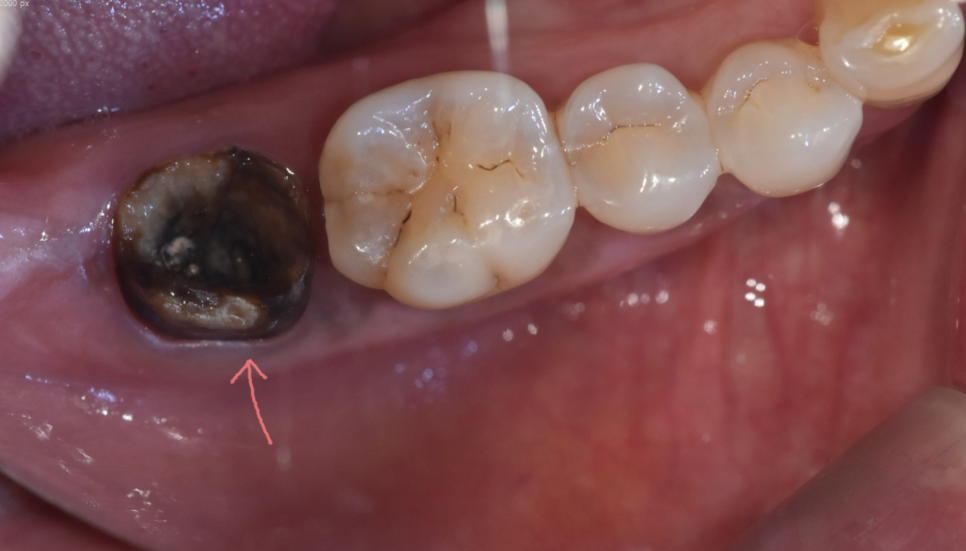

치아 내부가 충치가 심하거나

내부에서 깨져버리면 크라운을 다시 붙일 수 있는 지지대가 없어져

치료가 어려워집니다.

250327 내부 충치가 너무 심하면 발치 후 임플란트가 필요합니다.